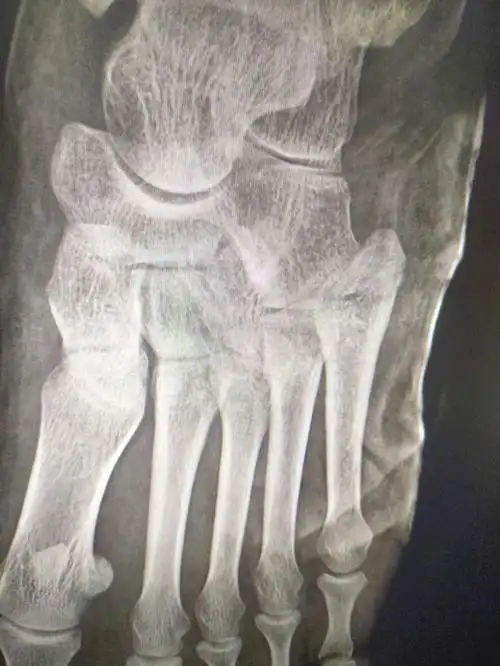

左脚跟骨粉碎性骨折如何冶疗好

跟骨骨折,46岁

左脚跟骨,骨折需要手术吗,懂行的帮我看哈

跟骨骨折做内固定手术俩月了,拍片看愈合的不错,现在能下地锻炼走了